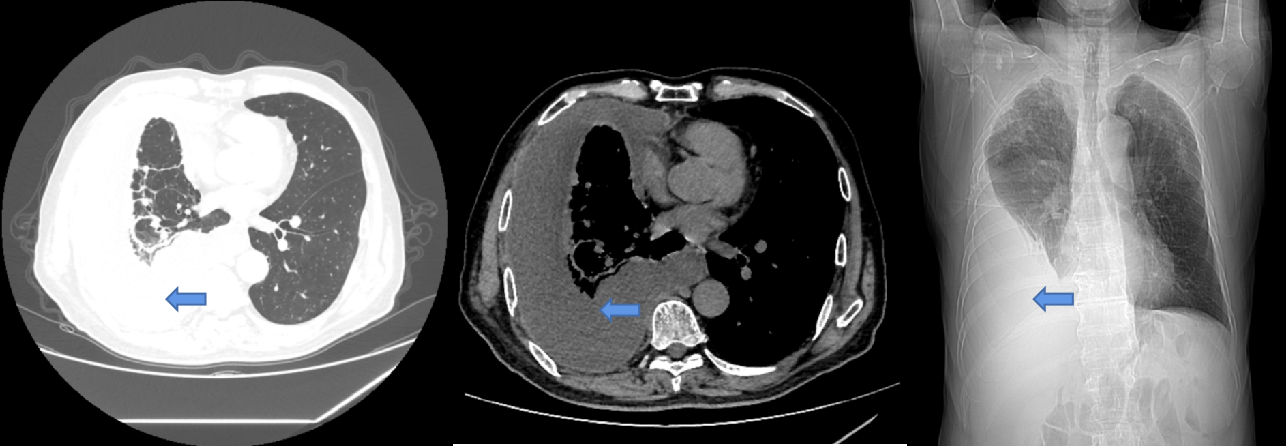

一名71岁男性患者,今年2月因“咳嗽、气促1月余”入住呼吸与危重症医学科,胸部CT显示:(图1)。胸腔积液超声(图2)显示胸水常规提示渗出液。

图1:胸部CT及胸片见右侧胸腔积液(蓝色箭头为胸腔积液)